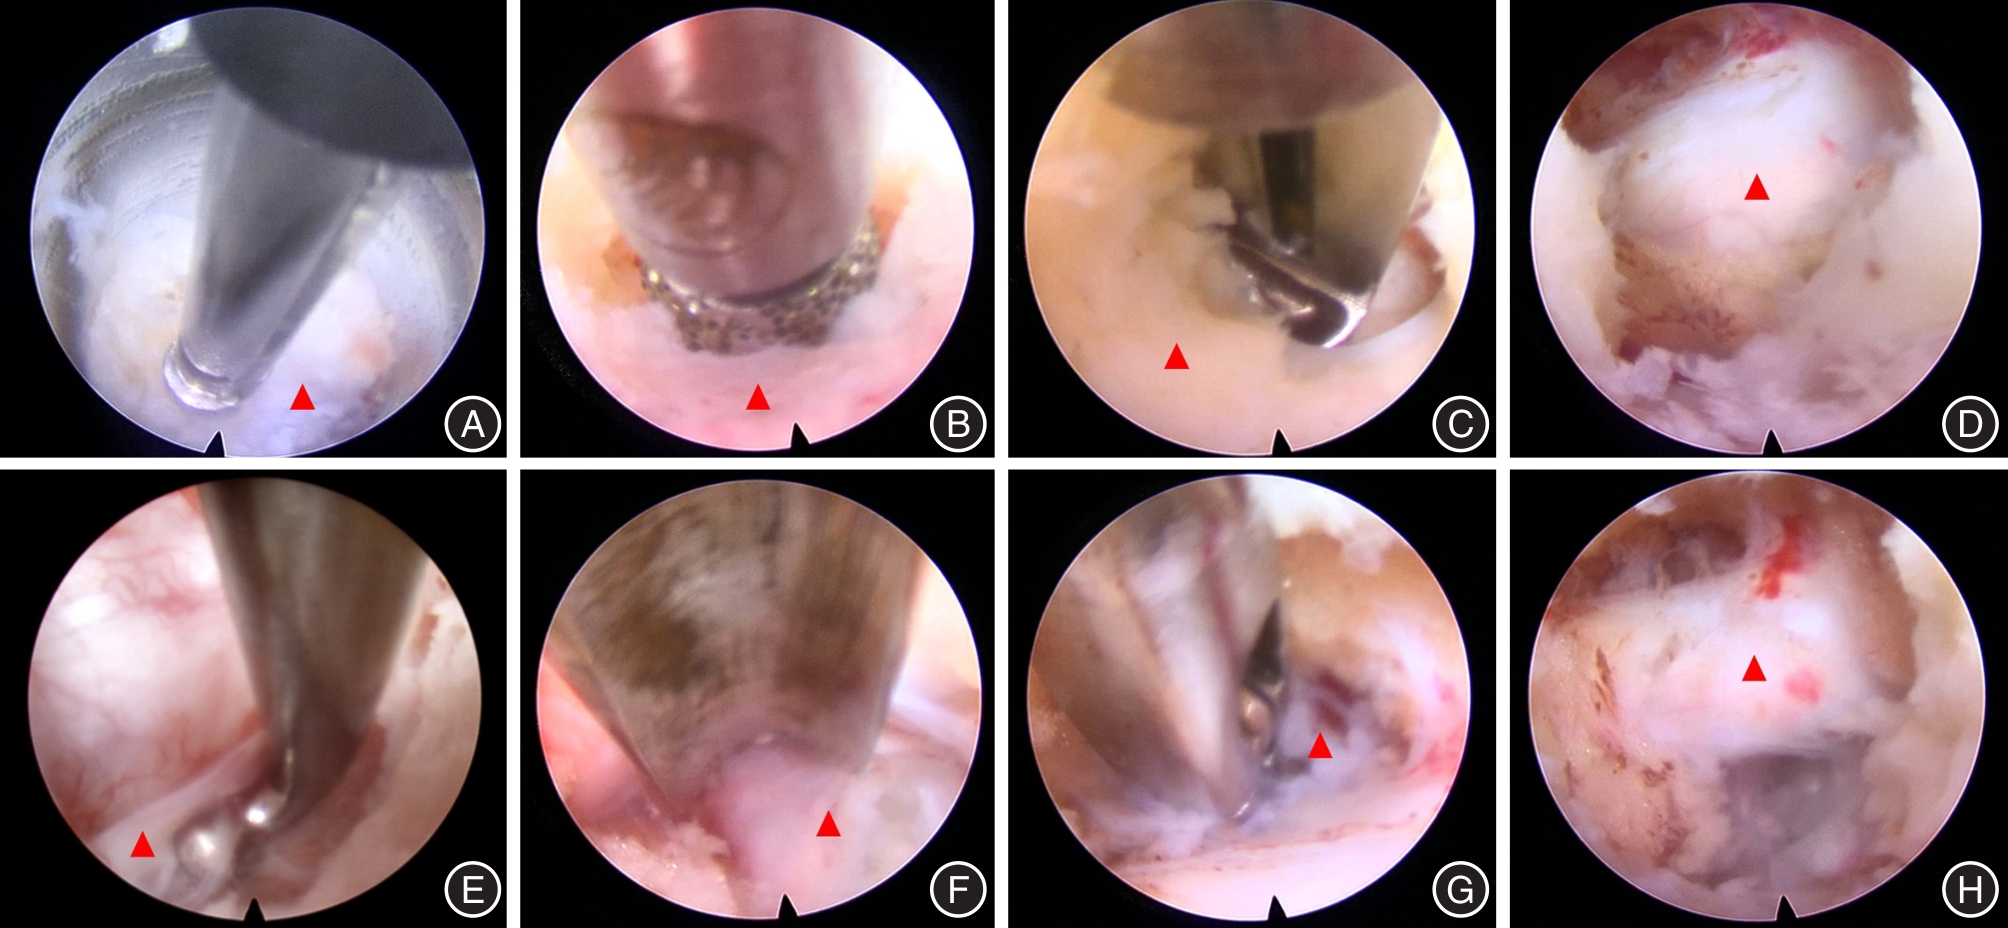

JIANG Q, DING Y, LU Z, et al. Comparative Analysis of Non-Full and Full Endoscopic Spine Technique via Interlaminar Approach for the Treatment of Degenerative Lumbar Spinal Stenosis: A Retrospective, Single Institute, Propensity Score-Matched Study[J]. Global Spine J, 2023,13(6):1509-1521. doi:10.1177/21925682211039181

17 | 蒋强,丁宇,卢正操,等. PE-MFD与Endo-LOVE治疗腰椎间盘突出症疗效比较[J]. 中国骨与关节损伤杂志, 2021, 36 (1): 13-16. |

24 | 朱凯,田照民,白杰,等. 全内镜下椎板开窗术治疗退行性腰椎侧隐窝狭窄症[J]. 中国骨伤, 2023, 36 (1): 5-11. |